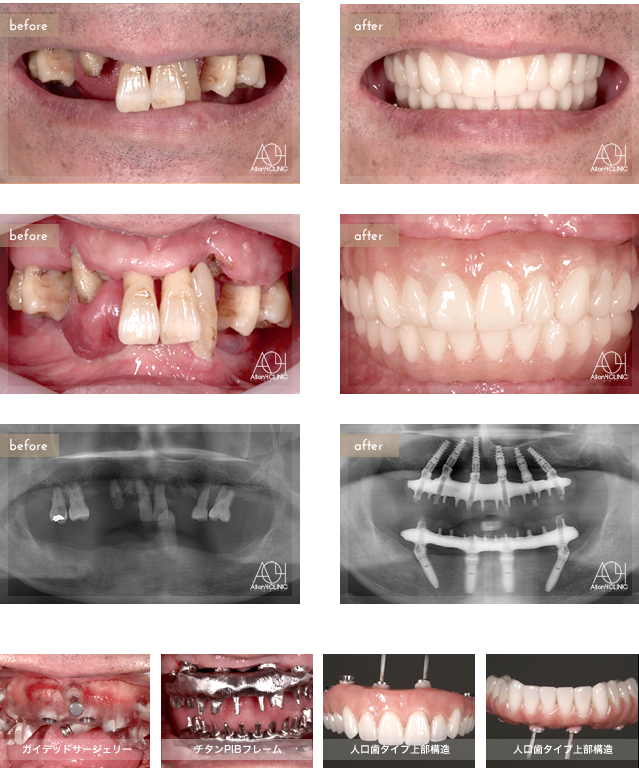

Age : 61

Sex : male

Treatment : 2012

-Maxilla All-on-4

- Under All-on-4

上顎は6本のNobel Activeインプラントを、 下顎はSpeedy Groovyを埋入。上下とも上部構造はチタンPIBフレーム人工歯タイプ (歯肉:アクリリックレジン 歯:人工歯)